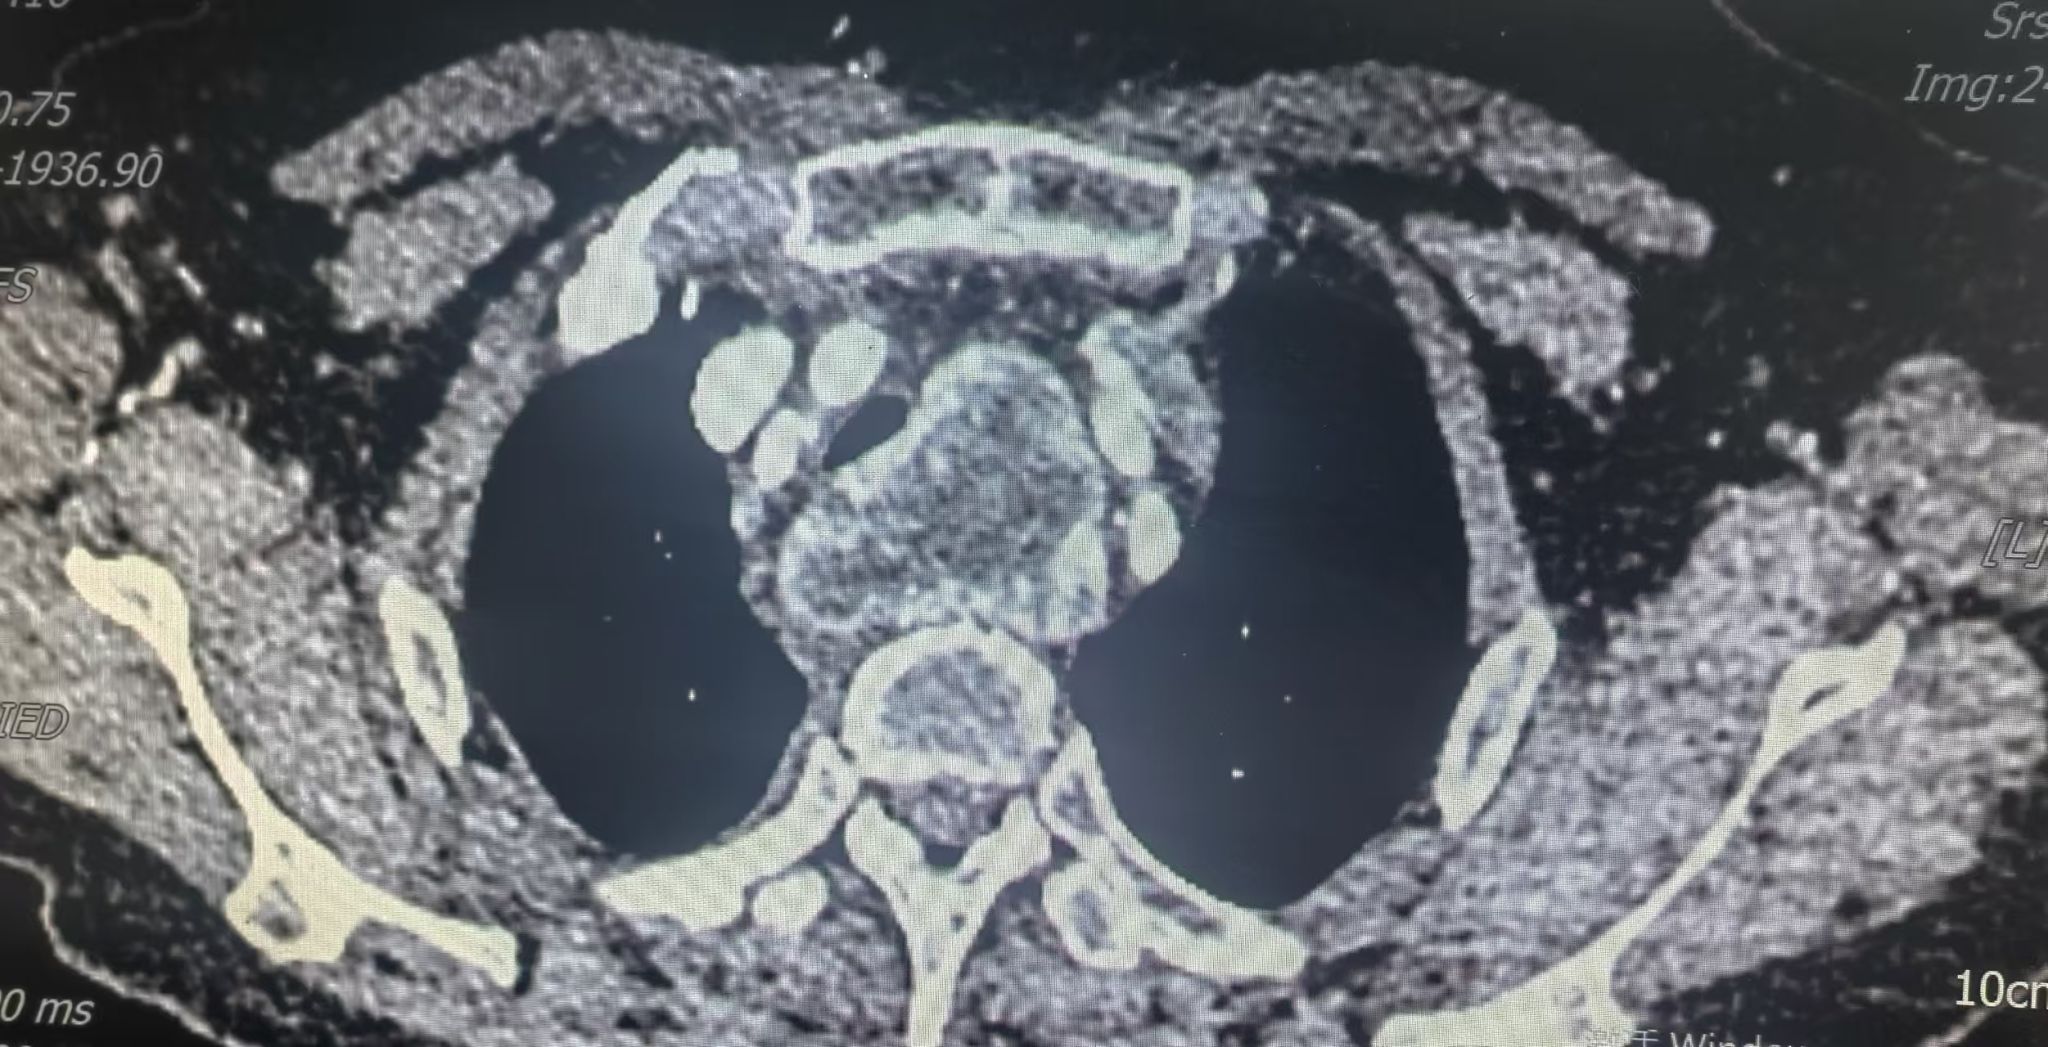

患者3 年前体检发现纵隔肿瘤,近期复查显示,上纵隔、甲状腺左侧叶后下方有一约 78mm×49mm×44mm 的团块状异常强化病灶,邻近气管、食管及主动脉弓分支受压移位,手术空间狭小且周围血管神经丰富,稍有不慎便可能造成严重并发症,对手术团队的技术和心理素质都是极大考验。

面对复杂病情,胸外科团队多次组织病例讨论。经全面评估患者病情,团队精准判断,选择经正中入路胸骨劈开的手术方式。该入路能为术者提供宽阔、直接的手术视野,便于在复杂的纵隔结构中精准操作,术中也证实此入路为该患者最恰当的手术方式。